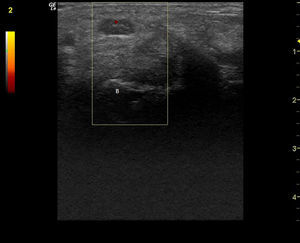

Observación clínicaMujer de 84 años, hipertensa controlada, presentaba desde hace 2 meses lesiones cutáneas en ambas manos de tipo vasculítico asociadas a cianosis del 1.er, 2.° y 3.° dedos, y a dolor intenso que motivaron hospitalización en urgencia por sospecha de vasculitis sistémica. En la anamnesis dirigida, no había elementos de conectivopatía ni consumo de drogas. Recibía enalapril para tratar su hipertensión arterial. En el examen físico destacaban lesiones periungueales, en pulpejos, indicativas de vasculitis, pero llamaba la atención su distribución dermatómica, la severa hipoestesia asociada en el mismo territorio y la importante atrofia de la eminencia tenar, de manera bilateral (fig. 1). El resto del examen era normal; en particular, no había lesiones cutáneas en otras localizaciones y su tensión arterial era normal. Se realizó estudio: hemograma y velocidad eritrocitaria de sedimentación normales, función renal y orina completa normales, factor reumatoideo negativo, anticuerpos antinucleares negativos, perfil ENA detallado negativo, ANCA c y p negativos. La paciente refería de alteraciones de la sensibilidad con parestesias nocturnas y falta de fuerza en manos con tiempo de evolución prolongado, por lo que ya había consultado. Se había hecho el diagnóstico de STC, realizándose una electromiografía de extremidades superiores un año antes. Esta mostraba ya un severo atrapamiento de ambos nervios medianos a nivel de los túneles carpianos, con denervación completa de las eminencias tenares. Se realizó estudio ultrasonográfico de la paciente evidenciando a la entrada del túnel a nivel del pisiforme, un nervio mediano derecho de 17mm2 de área (normal=± 10mm2)1,2 (fig. 2), con presencia central de una arteria mediana remanente (fig. 3). El nervio mediano izquierdo estaba también engrosado, con un área nivel del pisiforme de 18mm2. Ambos nervios aparecían atrapados en el túnel carpiano en los cortes longitudinales (fig. 4).

Corte transversal del nervio mediano derecho a nivel de la entrada del túnel del carpo, con medición del área del nervio con elipse (0,17cm2), a nivel del pisiforme P (B: hueso grande). (Imagen obtenida con ecógrafo General Electrics LOGIC e, con un transductor linear de 8-12 mHz usando para esta imagen una frecuencia de 12 mHz y un agrandamiento máximo).